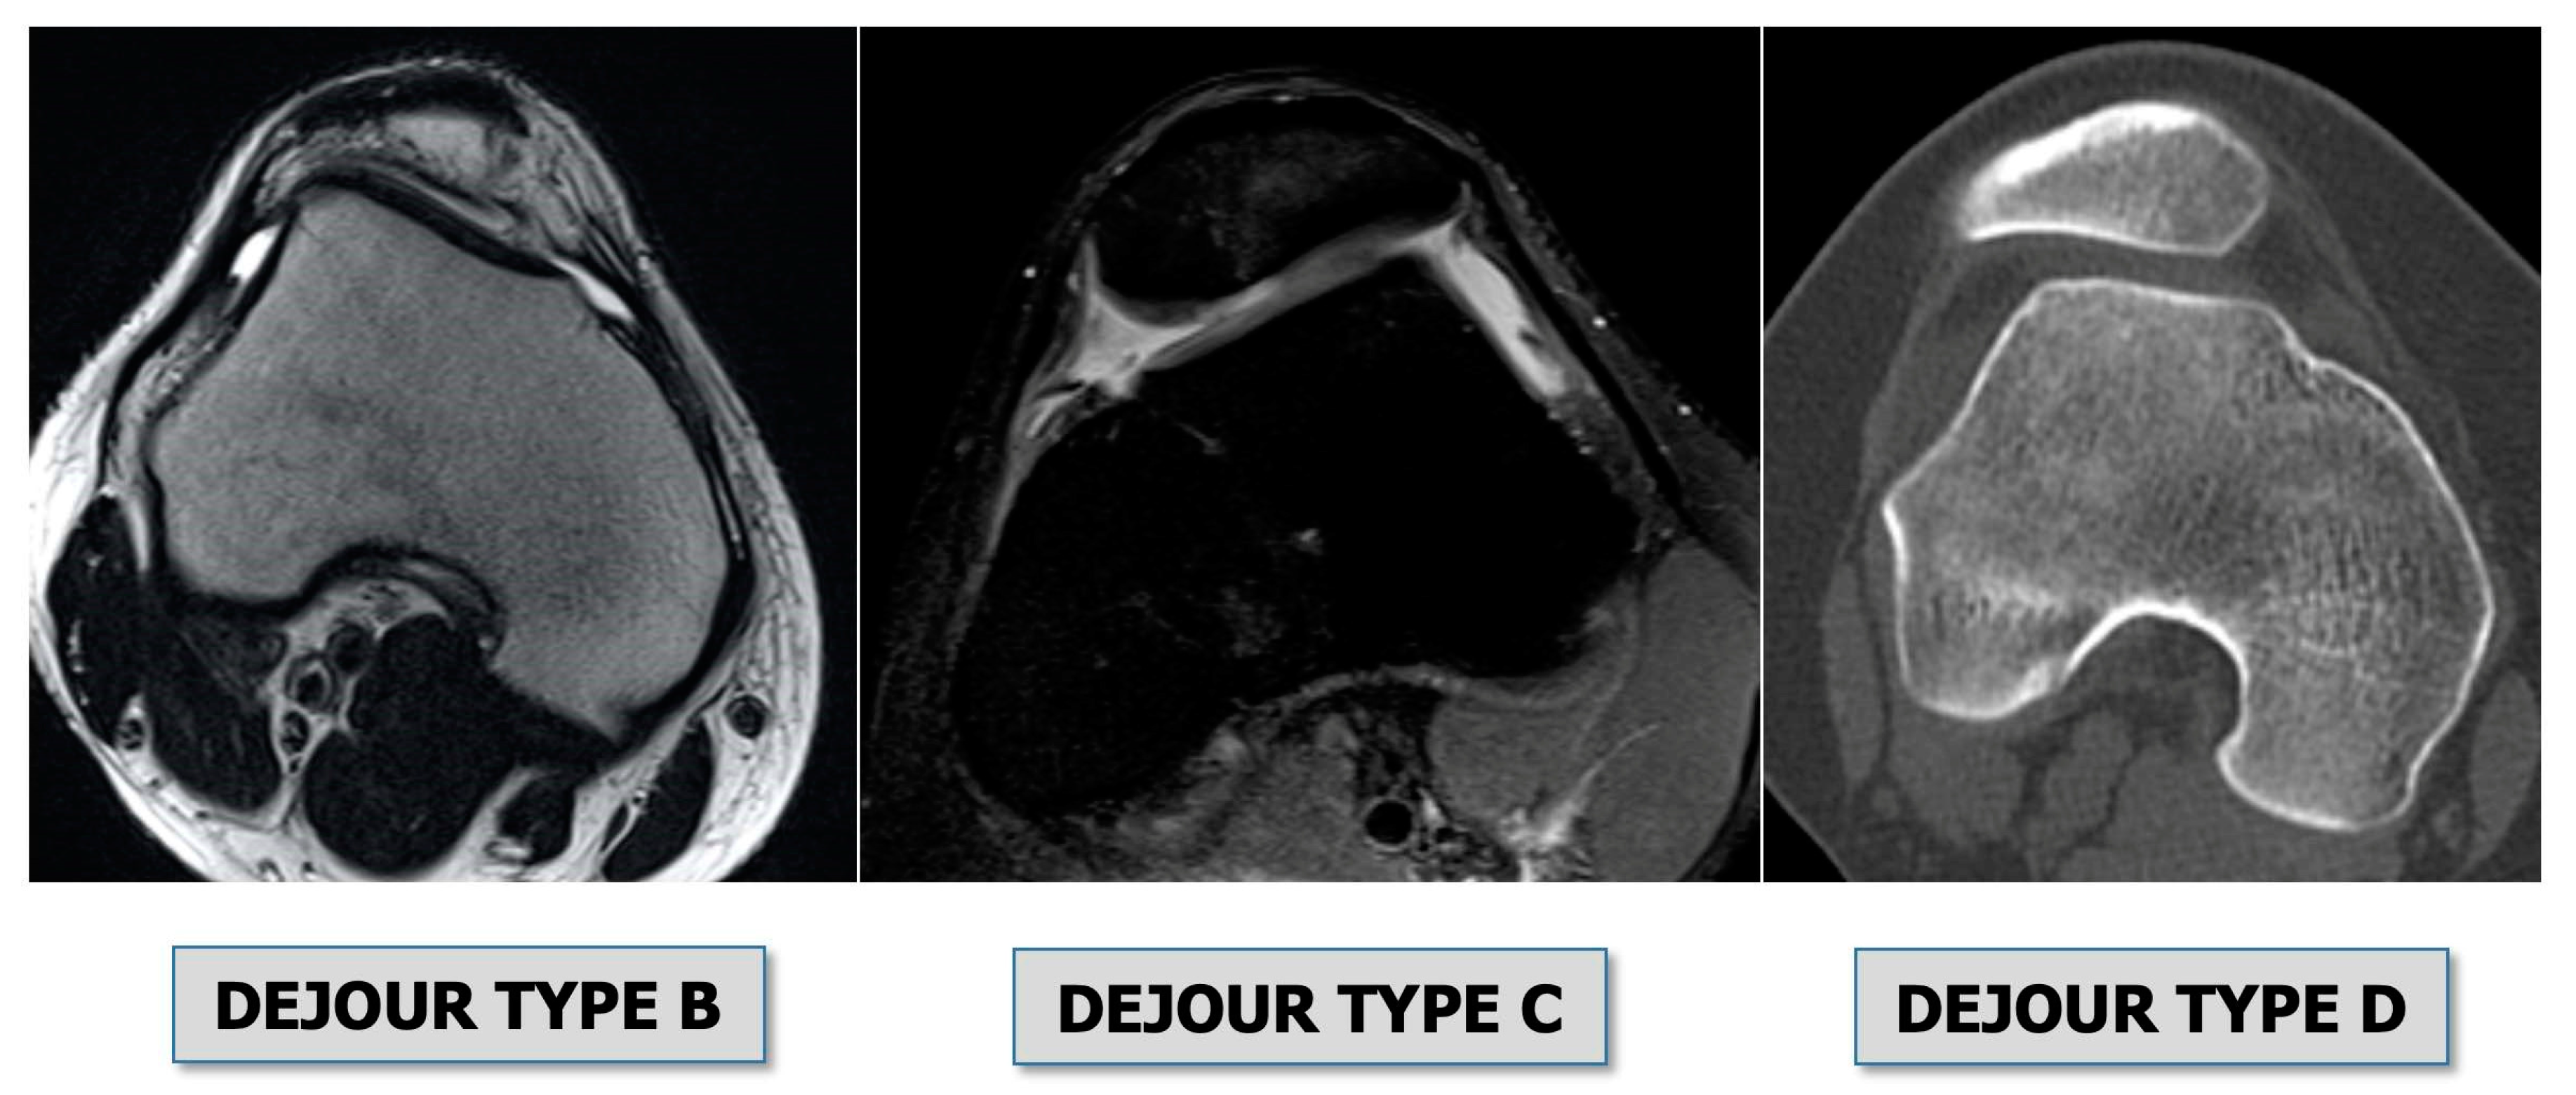

• Trochlear dysplasia: indicates how the femoral trochlea is flat or convex (instead of concave), causing abnormal patellar tracking and loss of joint congruence (Figure 1 and Figure 2). Dejour classified trochlear dysplasia into four groups [8]. This classification system requires an accurate lateral X-ray (congruent posterior condyles) and confirmation with axial imaging of the knee (CT scan or MRI). A certain degree of trochlear dysplasia was found in up to 96% of patients with objective or potential patellar instability [7].

Figure 1. Dejour classification of trochlear dysplasia on axial view [7]. Type A) Flattening of the trochlea (sulcus angle > 145°), but concavity is preserved. Type B) Lateral facet is flat to convex with a possible supratrochlear spur. Type C) Medial facet is hypoplastic, and the lateral facet is convex. Type D) Complete flattening of the trochlea with a marked depression on the medial facet (cliff sign).

Figure 2. Types trochlear dysplasia on MRI axial view, classified by Dejour [7].